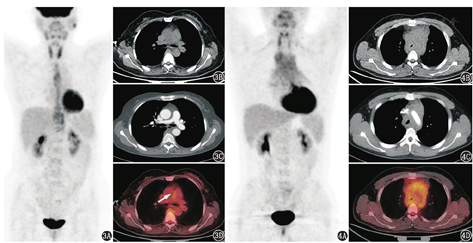

按照纵隔组织的来源来分析,常见的包括血管来源、淋巴结来源、神经源性或者间质来源的病变。由于病变的形态是包绕大血管和在脊柱两侧的条片状影,未形成明确的占位性肿物,所以暂不考虑实体性肿瘤;而病变在大血管周围和脊柱两侧的分布特点,首先考虑到主动脉周围炎、纵隔纤维化这类病变,因为大血管周围、脊柱两侧是这类病变典型的受累部位。主动脉周围炎和纵隔纤维化可以是免疫球蛋白(immunoglobulin, Ig)G4相关性疾病的表现之一[1],也可以独立存在,其表现与腹膜后纤维化相似,只是累及范围有不同,有时腹膜后纤维化可与纵隔纤维化的病变相延续。纵隔纤维化是增生的纤维组织包裹、浸润和压迫邻近的纵隔结构,可导致肺血管、上腔静脉等纵隔内大血管和支气管狭窄,可分为局灶性病变和弥漫型病变。局灶型纵隔纤维化多表现为局限性软组织肿块,常位于气管旁、隆突下或肺门区域,引起邻近血管或气道狭窄、梗阻,病灶内多伴钙化,需与相应部位的实体肿瘤相鉴别;而弥漫型病变多包绕或侵犯纵隔内多个结构,后纵隔脊柱两侧是常见的受累区域。如图3所示1例弥漫型纵隔纤维化患者,主要表现为后纵隔胸椎旁代谢增高的软组织密度影,并可见肺动脉干局部周围炎,病变累及范围尤其是后纵隔病变与本例患者相似。

除纵隔纤维化外,血液系统来源病变也容易累及中纵隔,并且有时也可能呈弥漫浸润性生长,受累组织可出现明显狭窄,甚至闭塞[3],但不形成明显的、边界清晰的肿块。如图4所示1例粒细胞肉瘤患者,表现为中后纵隔代谢增高的软组织密度影,病变包绕了主动脉弓和气管,致气管明显狭窄。与本例表现不同的是,这例粒细胞肉瘤患者的前纵隔胸腺区受累明显,而后纵隔脊柱两侧未见病变,提示可能为血液系统来源病变;另外病变对周围组织的浸润、压迫也更明显。除以上鉴别诊断外,患者有肺动脉狭窄、纵隔大血管周围包绕的软组织影,还要考虑到大动脉炎的可能,不过本例有脊柱两侧的病变,并不只是局限于大血管壁的病变,可暂时予以排除。